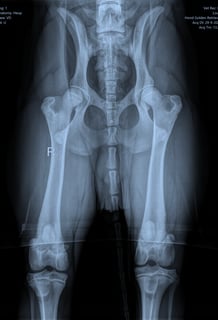

Gezondheid en Welzijn

We zijn trots om te kunnen zeggen dat Louie volledig gecontroleerd is op heupdysplasie, een veelvoorkomend probleem bij veel hondenrassen, en dat hij helemaal gezond is. Dit is cruciaal voor ons, omdat we willen garanderen dat Louie's nakomelingen gezond en sterk zijn.